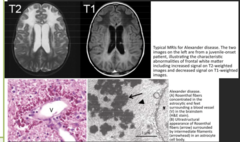

Alexander Disease (GFAP mutation, 17)

white matter abnormalities with a frontal predominance, glial fibrillary acid protein defect)codes for intermediate filament found in mature astrocytes...... bulbar symptoms in type 2, type 1: psychomotor retardation Rosenthal fibers